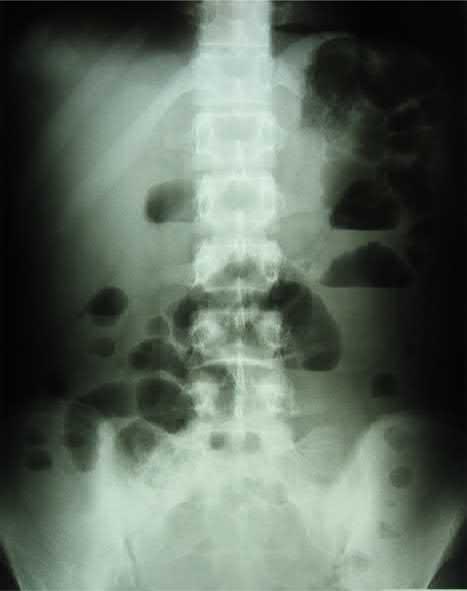

普通X线摄影检查可提示:节段性肠管扩张、气液平面、肠道的“拇纹征”或狭窄以及肠假性梗阻表现。

一个SLE病人发生了IPO,参考2